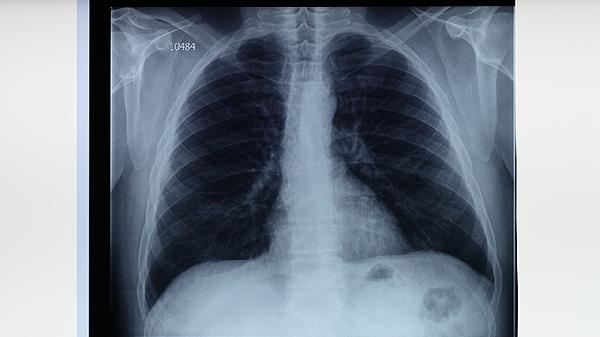

预防肺结核的关键是增强免疫力,保持良好的生活习惯,如均衡饮食、适量运动和充足睡眠。接种卡介苗可降低感染风险,但并不能完全预防。若与肺结核病人有密切接触,建议进行结核菌素试验或胸部X光检查,以及时发现感染。